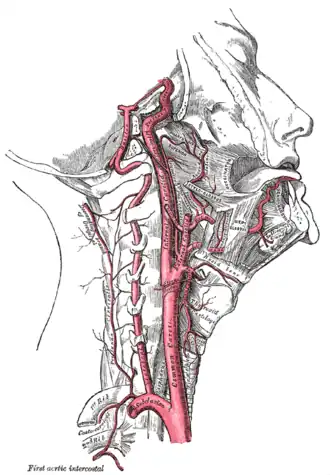

L'artère carotide interne (aussi appelée carotide interne droite ou CID) est une artère issue de l'artère carotide commune, de la branche externe plus précisément, et vascularisant la plus grande partie du cerveau, l'oreille interne et l'œil.

Dans le cou, elle est située dans la gaine carotidienne, à proximité de la veine jugulaire interne.

Elle pénètre dans la boîte crânienne par le canal carotidien situé dans le rocher (base du crâne) de l'os temporal selon un trajet vertical rétro styloïdien. Puis, dans son trajet pétreux, au niveau du foramen déchiré, elle donne dans le crâne une première branche collatérale qui est l'artère carotico-tympanique. En suivant, elle va transpercer le sinus caverneux, sortir par son toit et donner les dernières branches collatérales qui naissent près de la terminaison ; nous retrouvons l'artère cérébrale antérieure qui donnera l'artère hypophysaire supérieure ainsi que l'artère ophtalmique. De plus, dans cette région cérébrale, l'artère carotide interne va s'anastomoser avec l'artère cérébrale postérieure (dérivant de l'artère vertébrale) pour donner l'artère cérébrale moyenne du polygone de Willis.